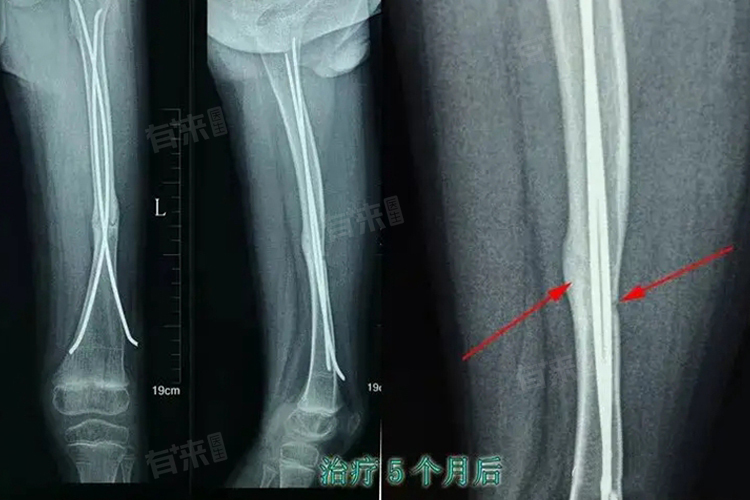

4、检查:

骨痂增生的检查方法主要包括X线检查、CT扫描和MRI等。X线检查可以清晰地显示骨骼结构和骨痂的形成情况,是诊断骨痂增生的首选方法。CT扫描可以提供更详细的骨骼图像,有助于评估增生的骨质范围和程度。MRI则主要用于评估软组织损伤和周围水肿情况。